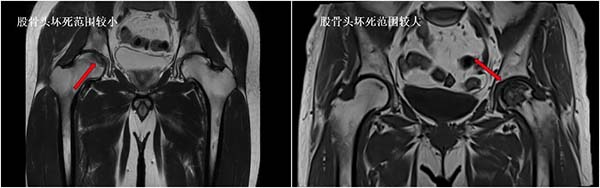

②坏死范围与位置:

除了分期,坏死的范围和位置也直接影响预后:

如果坏死范围小,且不在股骨头的“负重区”(走路、站立时承受压力的部位),股骨头不易塌陷,恢复更快,预后更好;反之,坏死范围大且位于负重区,极易出现塌陷,加重病情,预后大打折扣。